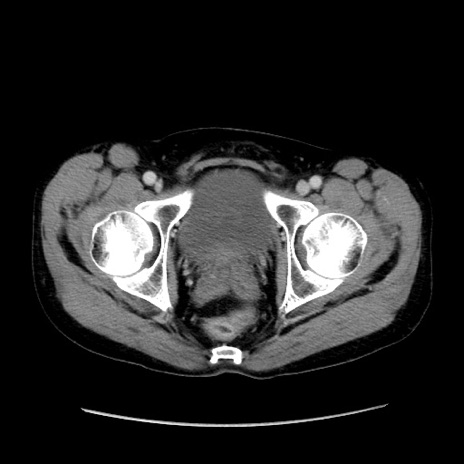

症例37(横断像)

【症例】40歳代 男性

【主訴】腹痛

【現病歴】4時間ほど前に電車に乗車中に臍部上より腹痛出現。徐々に増悪し起立困難となり、救急外来受診。生ものは数日食べていない。今朝お雑煮を食べた。

【身体所見】BT 36.8℃、BP 117/84mmHg、HR 91/min、SpO2 97%、苦悶様、腹部:臍上部広範囲圧痛あり、反跳痛±

【データ】WBC 8100、CRP 0.03